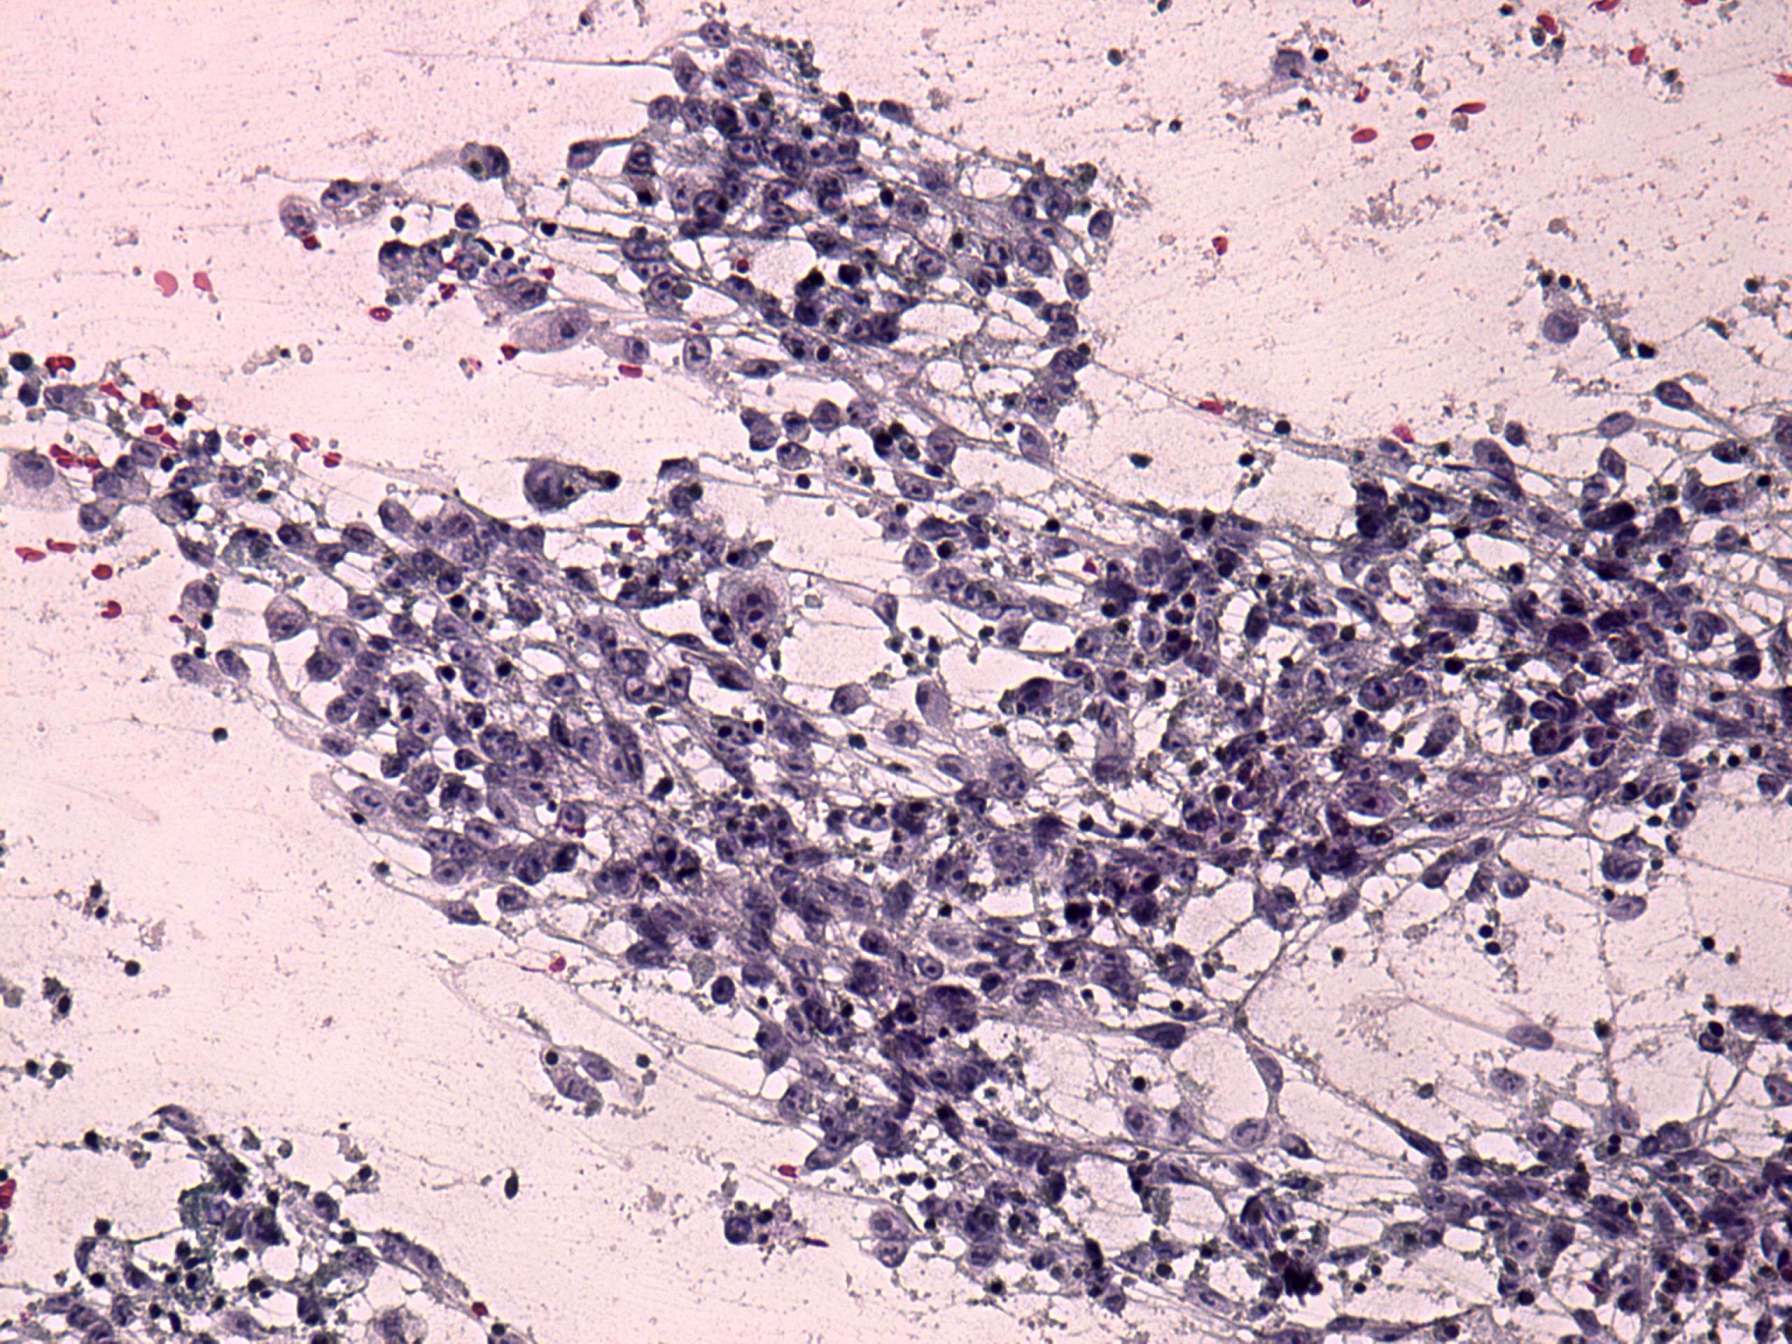

Lymph nodes in the neck - Case 1160 (cytologic picture 3)

Pap-smear, 200x.   Irregular clusters of elongated, cylindrical cells.